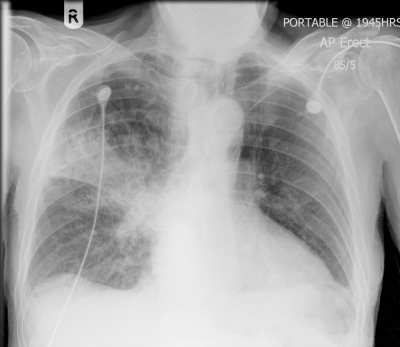

What does this CXR show?

This is a RUL consolidation - hints are that you can still see both